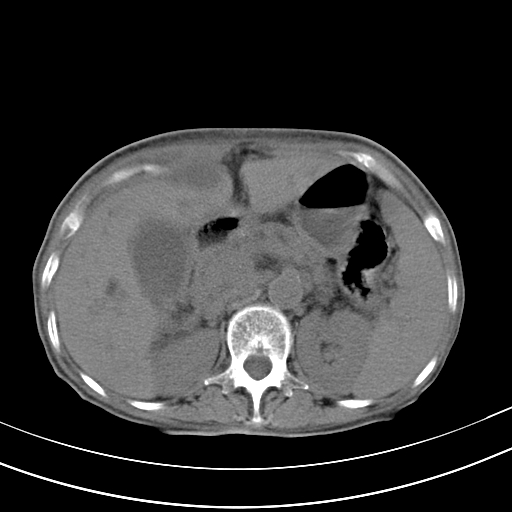

病人上腹部胀痛拌全身黄染八天

结石好象不明显吧?胆管稍扩张。

右侧少量胸水,胆囊增大,肝内胆管扩张,肝门部结构杂乱,建议增强。

考虑胰头癌或胰腺炎

肝内胆管及胰管扩张考虑为胰头区占位,肝门淋巴结增多,肝内多发低密度影,考虑为转移。门脉高压,脾大,胆囊大。

肝内胆管及胰管扩张,胰头增大考虑为胰头区占位,肝门淋巴结增多,考虑为转移。建议增强,脾大,胆囊大,壁厚,慢性胆囊炎。胃壁好像也增厚,且有一肿物。

1)考虑胰头癌并胆系低位梗阻;建议行ct增强扫描检查。2)慢性胆囊炎。3)脾大。4)少量腹水。5)双侧少量胸腔积液。